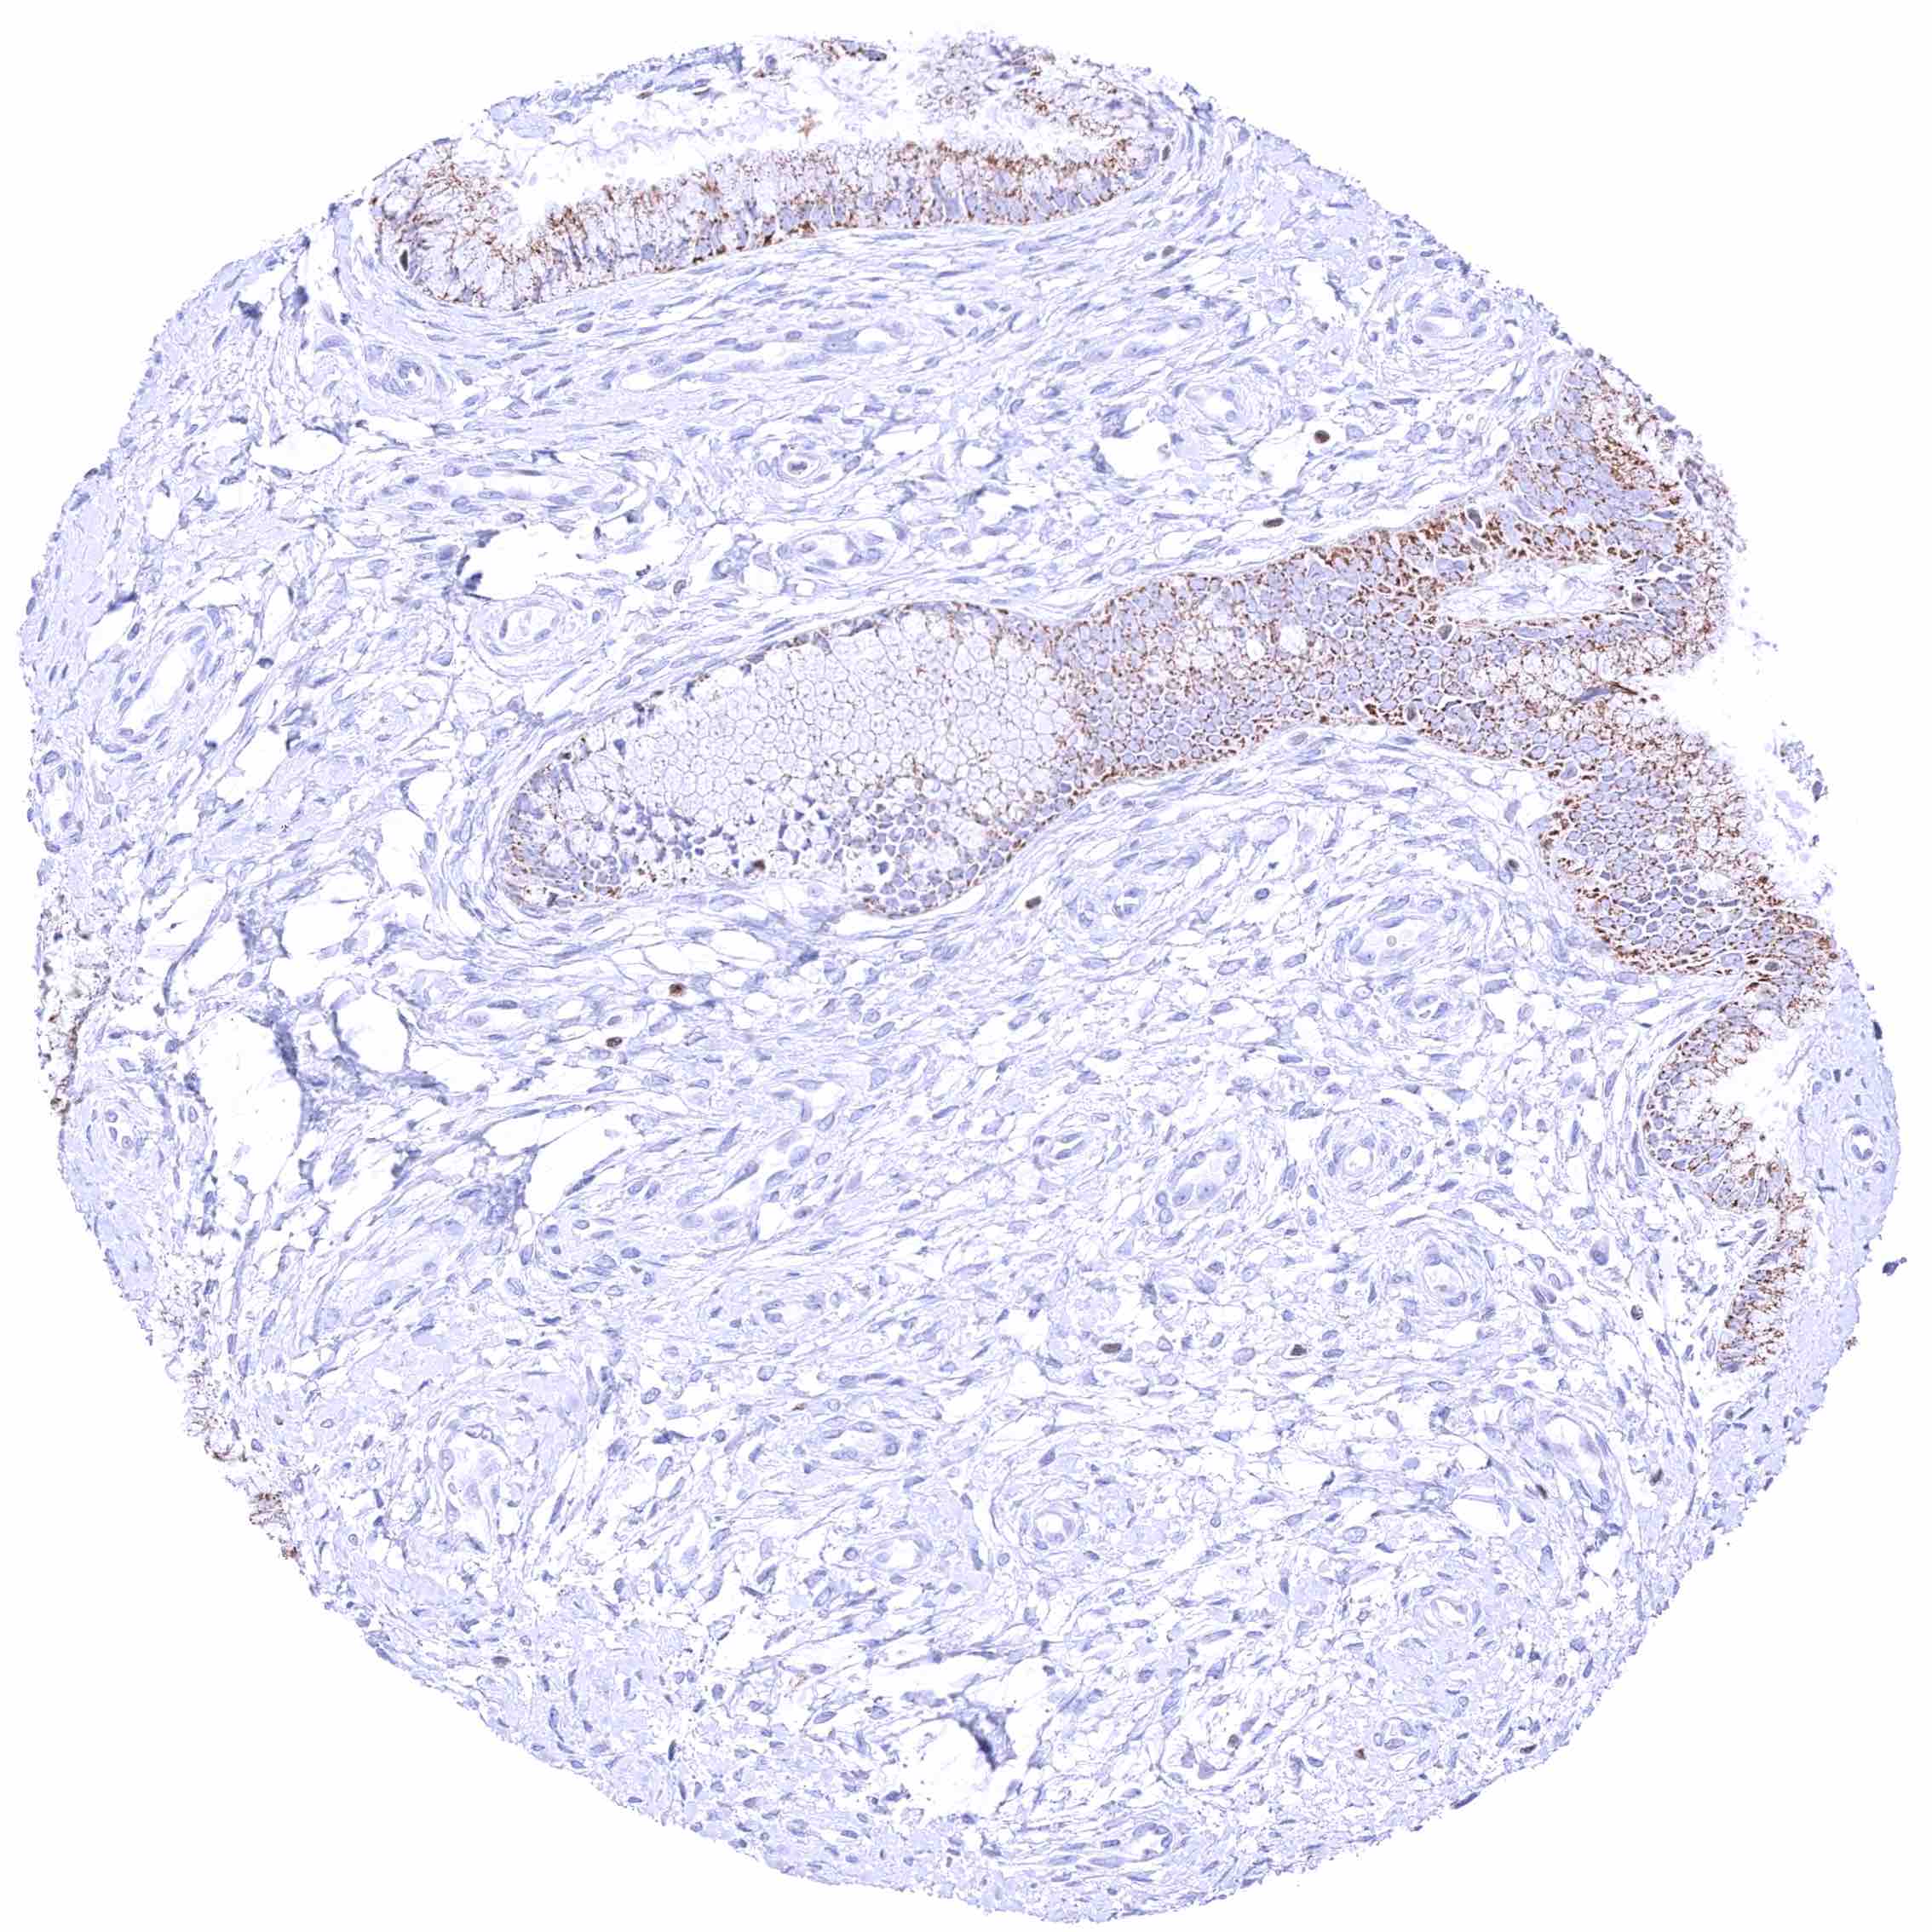

Skin – Strong nuclear GATA3 staining of squamous epithelial cells.

Skin, hair follicel and sebaceous glands – Strong nuclear GATA3 staining of squamous epithelial cells, cells of hair follicles, and peripheral germinative cells of sebaceous glands. Nuclear GATA3 staining is faint or absent in cells of sebaceous glands.